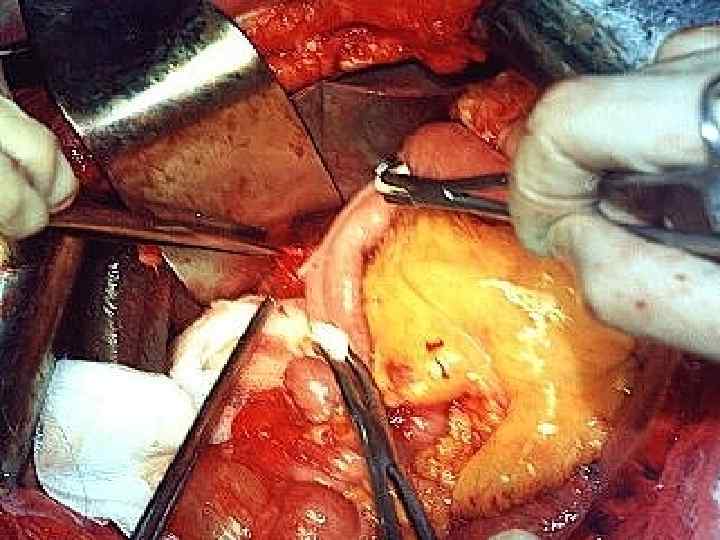

Этапы стандартной ГПДР • • • 1. Мобилизация 12 -перстной кишки 2. Выделение трубчатых структур гепато-дуоденальной связки 3. Выделение верхней брыжеечной вены 4. Мобилизация и отсечение дистальной части холедоха 5. Мобилизация и пересечение начальной части тощей кишки 6. Пересечение гепатикохоледоха после мобилизации желчного пузыря • 7. Пересечение поджелудочной железы по перешейку • 8. Пересечение связок крючковидного отростка, удаление комплекса • 9. Реконструктивный этап

Резекция чревного ствола и общей печёночной артерии при выполнении ДСРПЖ Вид резекции Циркулярная резекция чревного ствола Всего Число больных с пластикой 4 без пластики 11 15